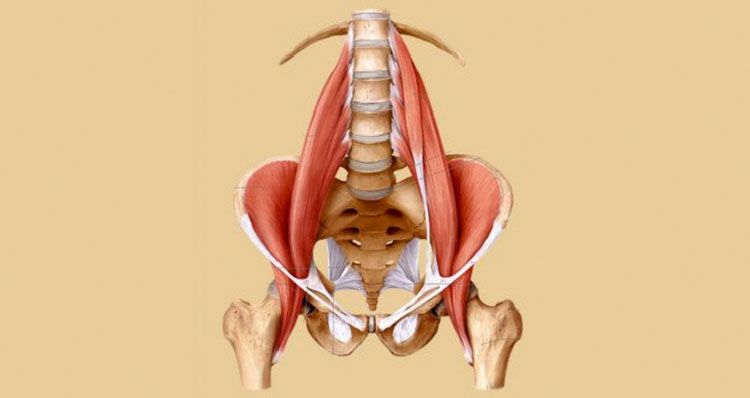

¿Dónde está el psoas?

El psoas es el músculo principal asociado con la estabilidad física. Se extiende desde las piernas hasta la columna vertebral y es el único músculo que conecta las piernas con la columna vertebral. El músculo comienza en la vértebra T12, continua por las cinco vértebras lumbares, antes de conectar a la parte superior del hueso del muslo (fémur).